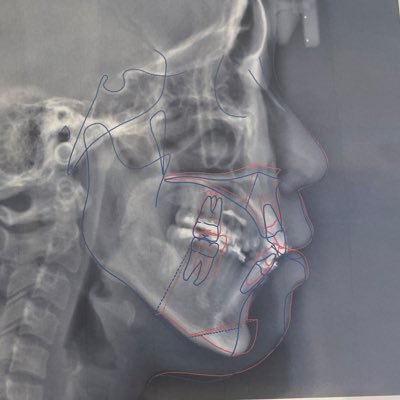

[顎変形症] 術前→両顎手術後1年→オトガイ形成後2週間の比較です! 鼻の変形、ほうれい線、頬こけとか色々悩みは増えて正面顔は嫌いやけど、横顔は圧倒的に綺麗になったので今のところ後悔してないです🤔 あとは下顎の麻痺がどこまでマシになるかな🥺 少しでも下顎後退の方の参考になれば!

テープ外してから鏡見るたび、顎!!!顔でか!!! ってなってちょっと病んでるけどまだ5日だから!と心を落ち着かせてる。 レントゲンで見る限り全然出し過ぎじゃないし(最大限出してくれた)顔の長さ自体は変わってないので大人しく腫れが引くのを待ちます🥺 赤丸部分は麻痺しててほとんど感覚ない